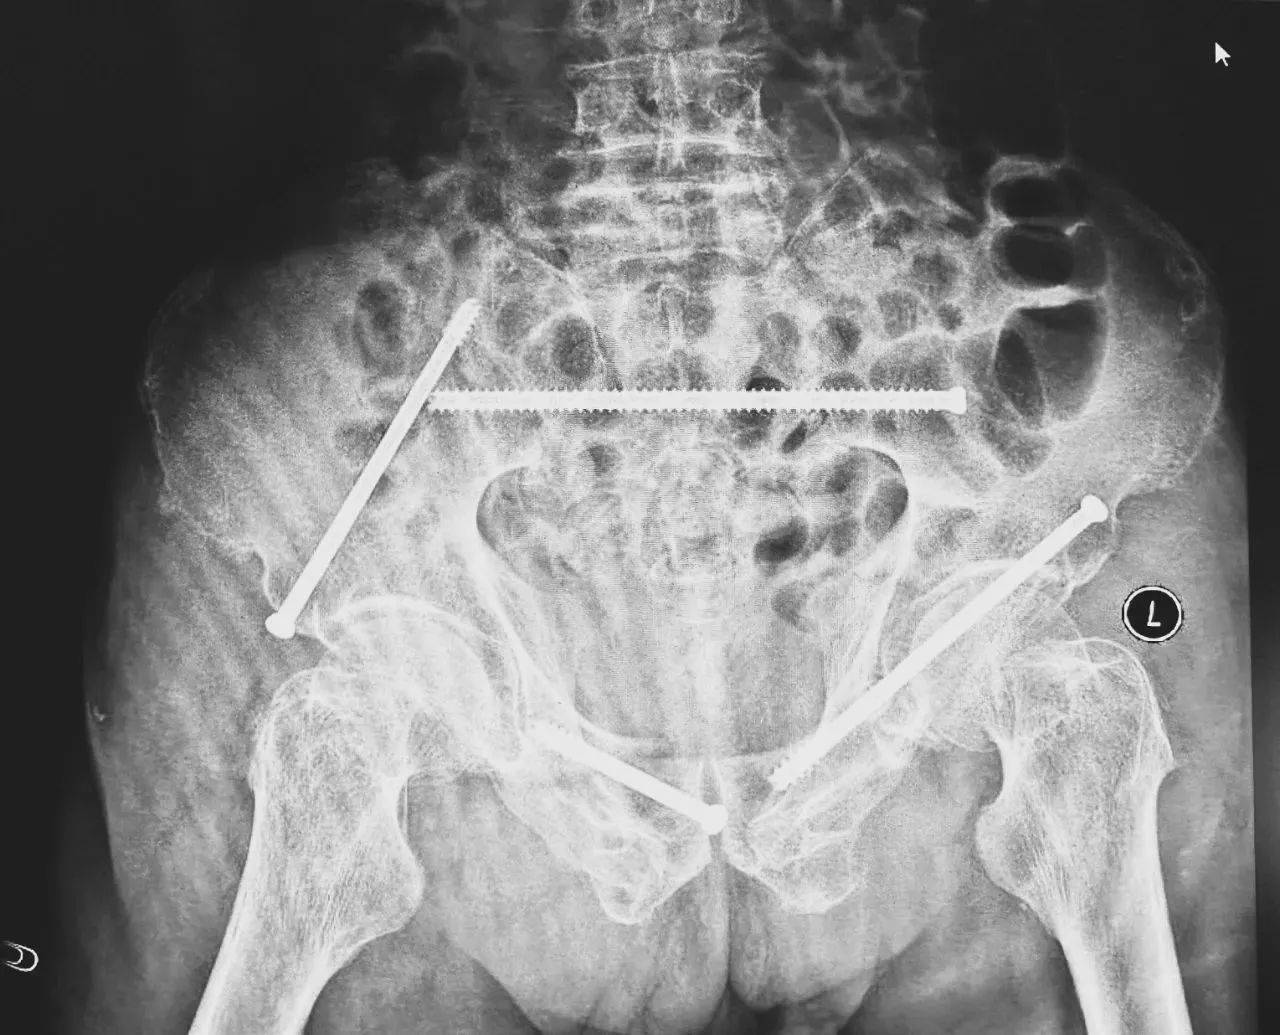

ÊõǰӰÏñѧÏÔʾ£¬£¬£¬£¬£¬»¼ÕßµÄ×ó²à÷¾¹Ç¹ÇÕÛ£¬£¬£¬£¬£¬ÓÒ²à³Ü¹Ç¹ÇÕÛ¡¢÷ĹǹÇÕÛ£¬£¬£¬£¬£¬¹ÇÅè¹ÇÕÛ·ÖÐÍΪCÐÍ£¬£¬£¬£¬£¬ÍíÄê´àÐÔ¹ÇÅè¹ÇÕÛ·ÖÐÍΪIVÐÍ£¬£¬£¬£¬£¬ÊǼ«¶Ë²»ÎȹÌÐ͵Äǰ»·¹ÇÕÛºÍË«²àºó»·¹ÇÕÛ¡£¡£¡£¡£¡£ËùÐÒûÓÐÏÔ×ŵĹÇÅè³öѪ»òÄÚÔàËðÉ˵ÄÌåÏÖ¡£¡£¡£¡£¡£

ÎÞÓ°µÆÏ£¬£¬£¬£¬£¬ÖÇÄܹǿÆÍŶӽ«»¼Õßʾ×ÙÆ÷£¬£¬£¬£¬£¬·ÅÔÚ×ó²à÷ÄǰÉϼ¬£¬£¬£¬£¬£¬Ê¹ÓÃÊõÖÐÈýάӰÏñ×°±¸»ñÈ¡¹ÇÅèµÄÈýάͼÏñ£¬£¬£¬£¬£¬É¨ÃèЧ¹û´«ÊäÖÁ»úеÈ˵¼º½ÏµÍ³£¬£¬£¬£¬£¬Íê³ÉÂݶ¤ÖÃÈëµÄλÖúÍ×ßÐΣ¬£¬£¬£¬£¬²¢ÔÚ»úеÈ˵ÄÖ¸µ¼Ï»®·ÖÖÃÈë4öͨµÀÂݶ¤¡£¡£¡£¡£¡£ÖÃÈëºóÔٴξÙÐÐCTɨÃèÑéÖ¤£¬£¬£¬£¬£¬Ö¤Êµµ¼Õë׼ȷÖÃÈë¡£¡£¡£¡£¡£

ÊõºóµÚ¶þÌ죬£¬£¬£¬£¬Ò½ÉúÍŶӸ´²éXƬÏÔʾÂݶ¤Ö²ÈëλÖúÜÊÇÖª×㣬£¬£¬£¬£¬¹ÇÕÛ»ù±¾µÖ´ïÎȹ̸´Î»£¬£¬£¬£¬£¬Í¬Ê±£¬£¬£¬£¬£¬¸´²éµÄȫѪϸ°û¼ÆÊýÖУ¬£¬£¬£¬£¬ÑªºìÂѰ×Ö¸ÊýΪ102g/L¡£¡£¡£¡£¡£ÊõºóµÚÈýÌ죬£¬£¬£¬£¬ÔÚÖÇÄܹǿƲ¡·¿Õչ˻¤Ê¿ÍŶӼ°¿µ¸´Ê¦µÄÖ¸µ¼ºÍÕչ˻¤Ê¿Ï£¬£¬£¬£¬£¬Íõ´óÒ¯¿ÉÒÔ×øÁ¢ÔÚ´²ÉÏ¡£¡£¡£¡£¡£ÊõºóµÚËÄÌ죬£¬£¬£¬£¬Íõ´óÒ¯ÓÀ´Á˳öÔºÈÕ£¬£¬£¬£¬£¬¡°µÃ¿÷ÓÐÁËÕâôÏȽøµÄÒ½ÁÆÊÖÒÕ£¬£¬£¬£¬£¬ÈÃÎÒ»¹ÄÜϵØÐÐ×ߣ¬£¬£¬£¬£¬Ð»Ð»ÄãÃÇ£¡¡±